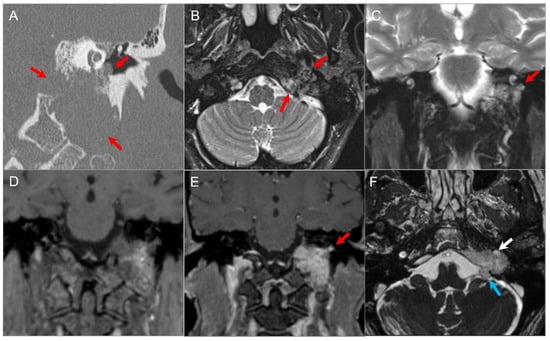

4.4.4. Endolymphatic Sac Tumor

4.4.5. Paraganglioma